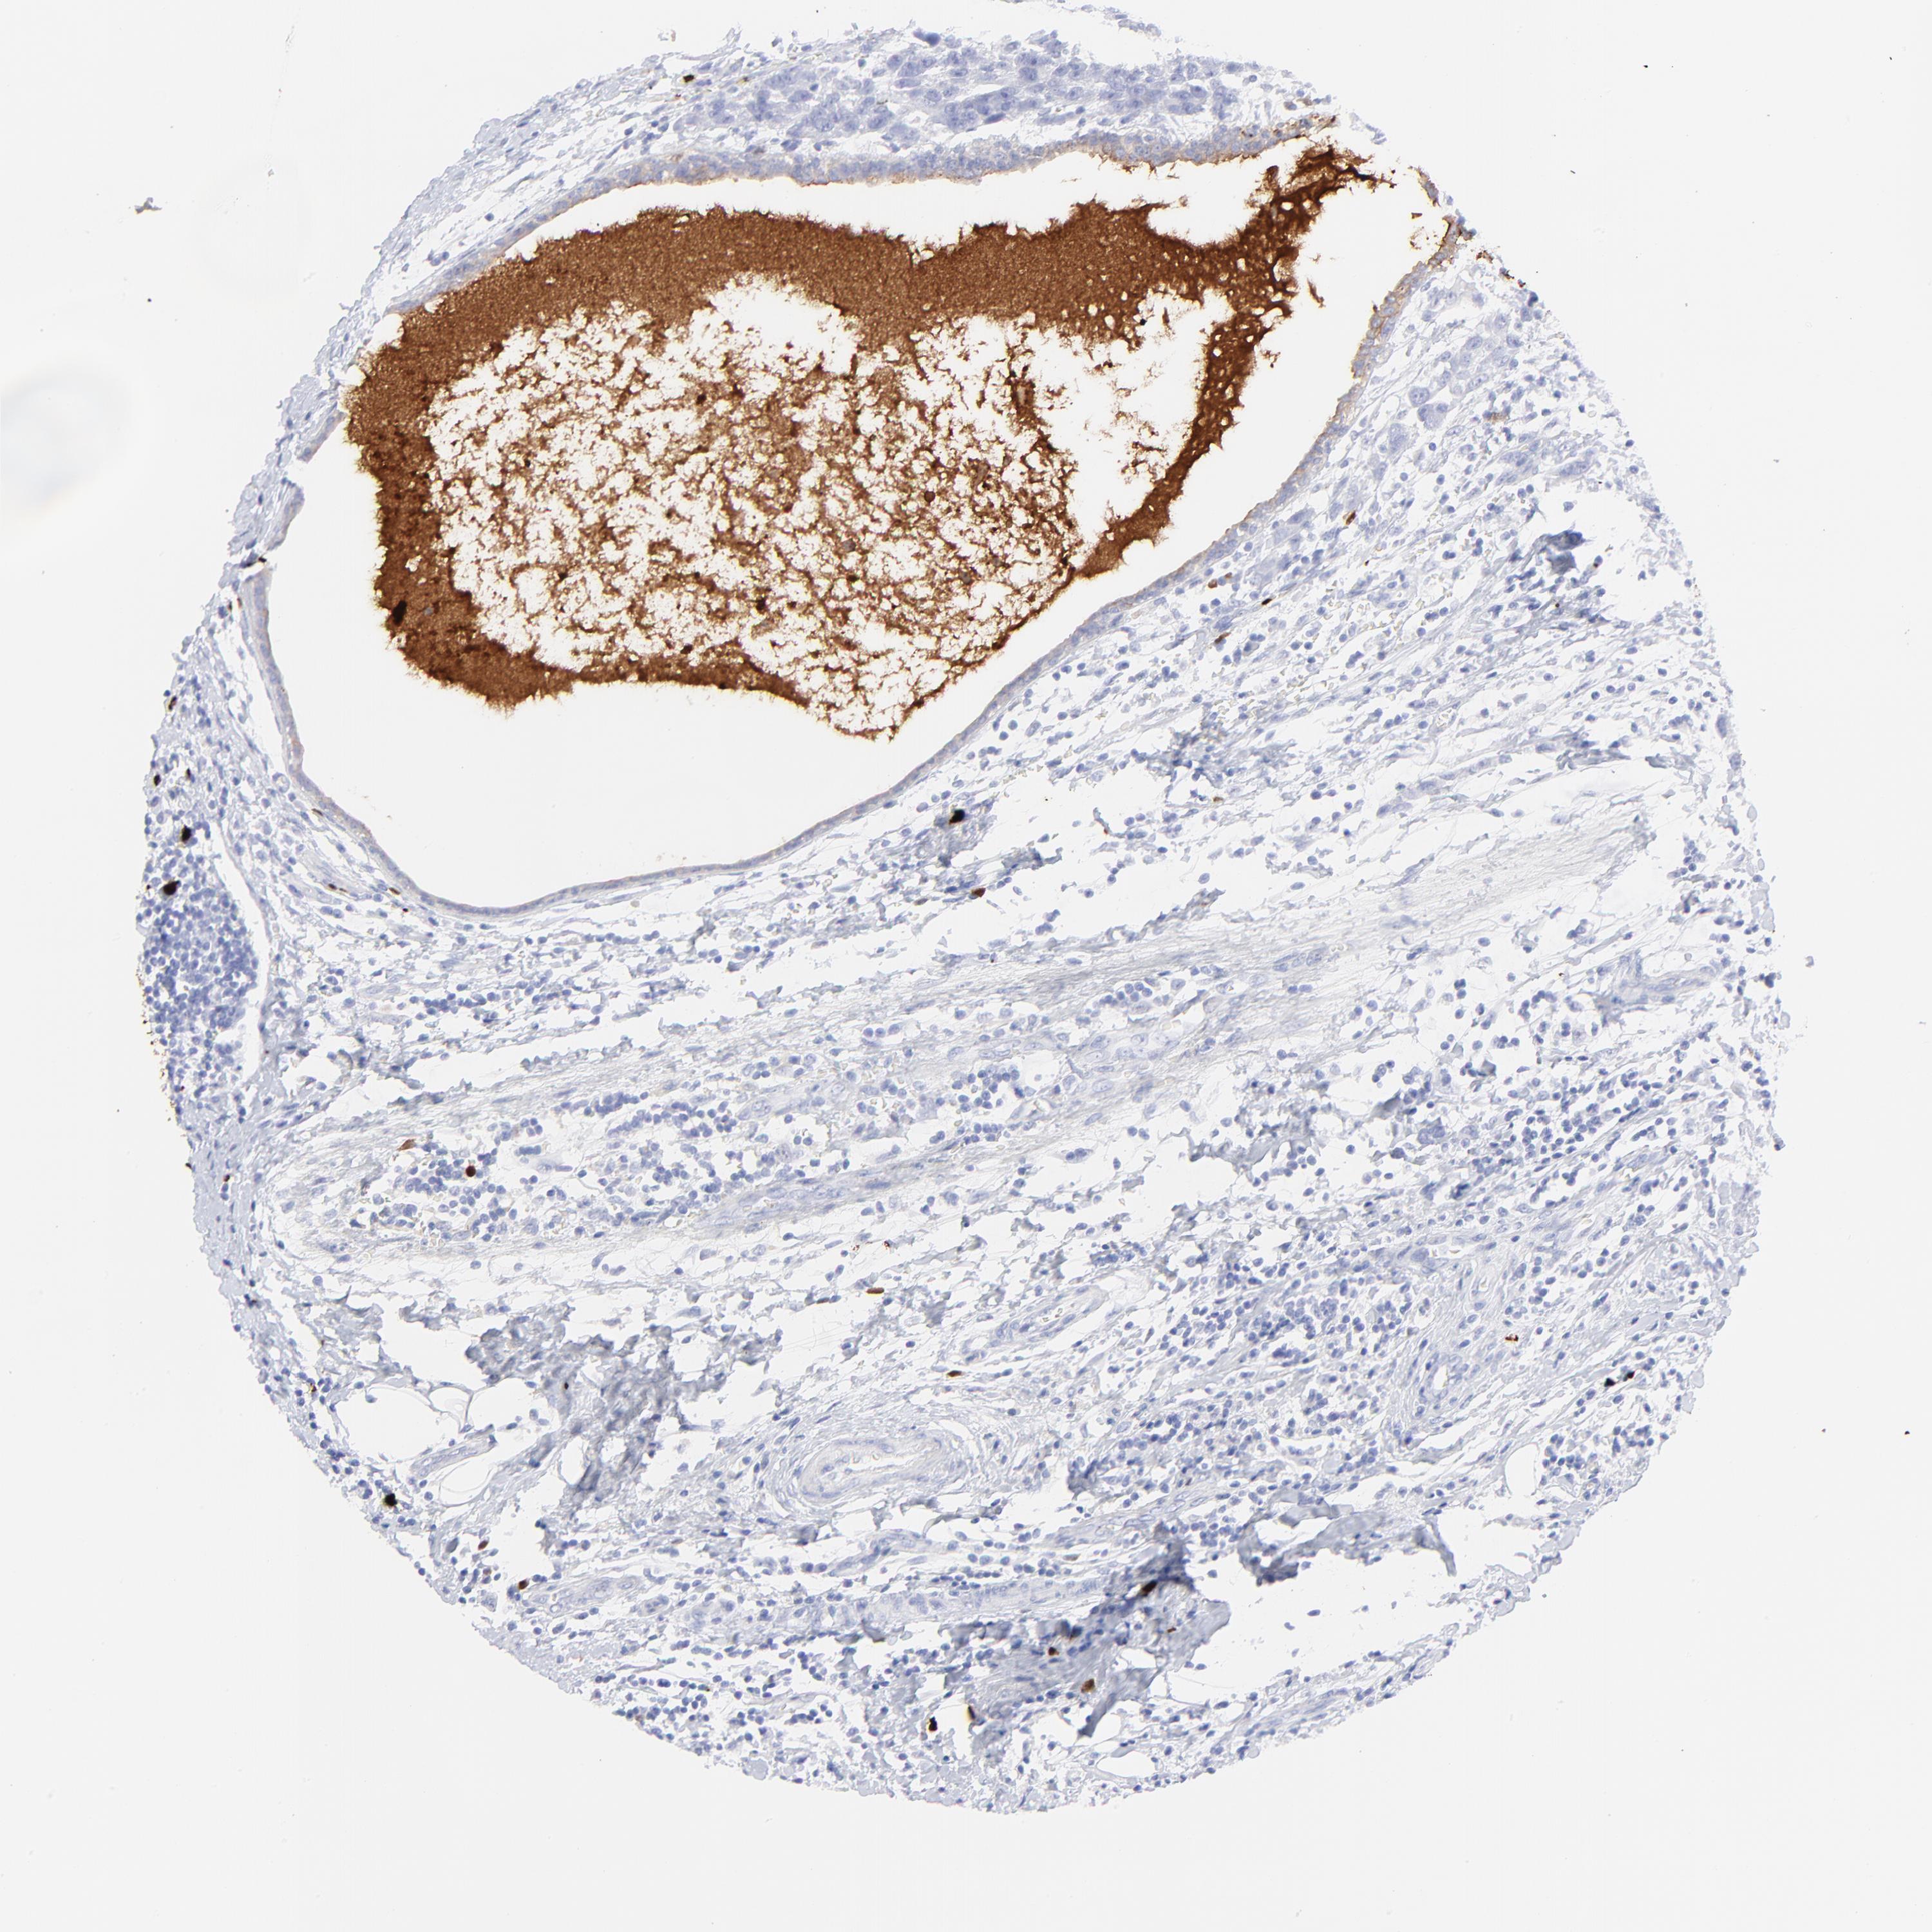

CANCER BREAST CANCER Show tissue menu

BRCA TCGA BRCA VALIDATION PROTEIN EXPRESSION

ANTIBODIES

AND

VALIDATION